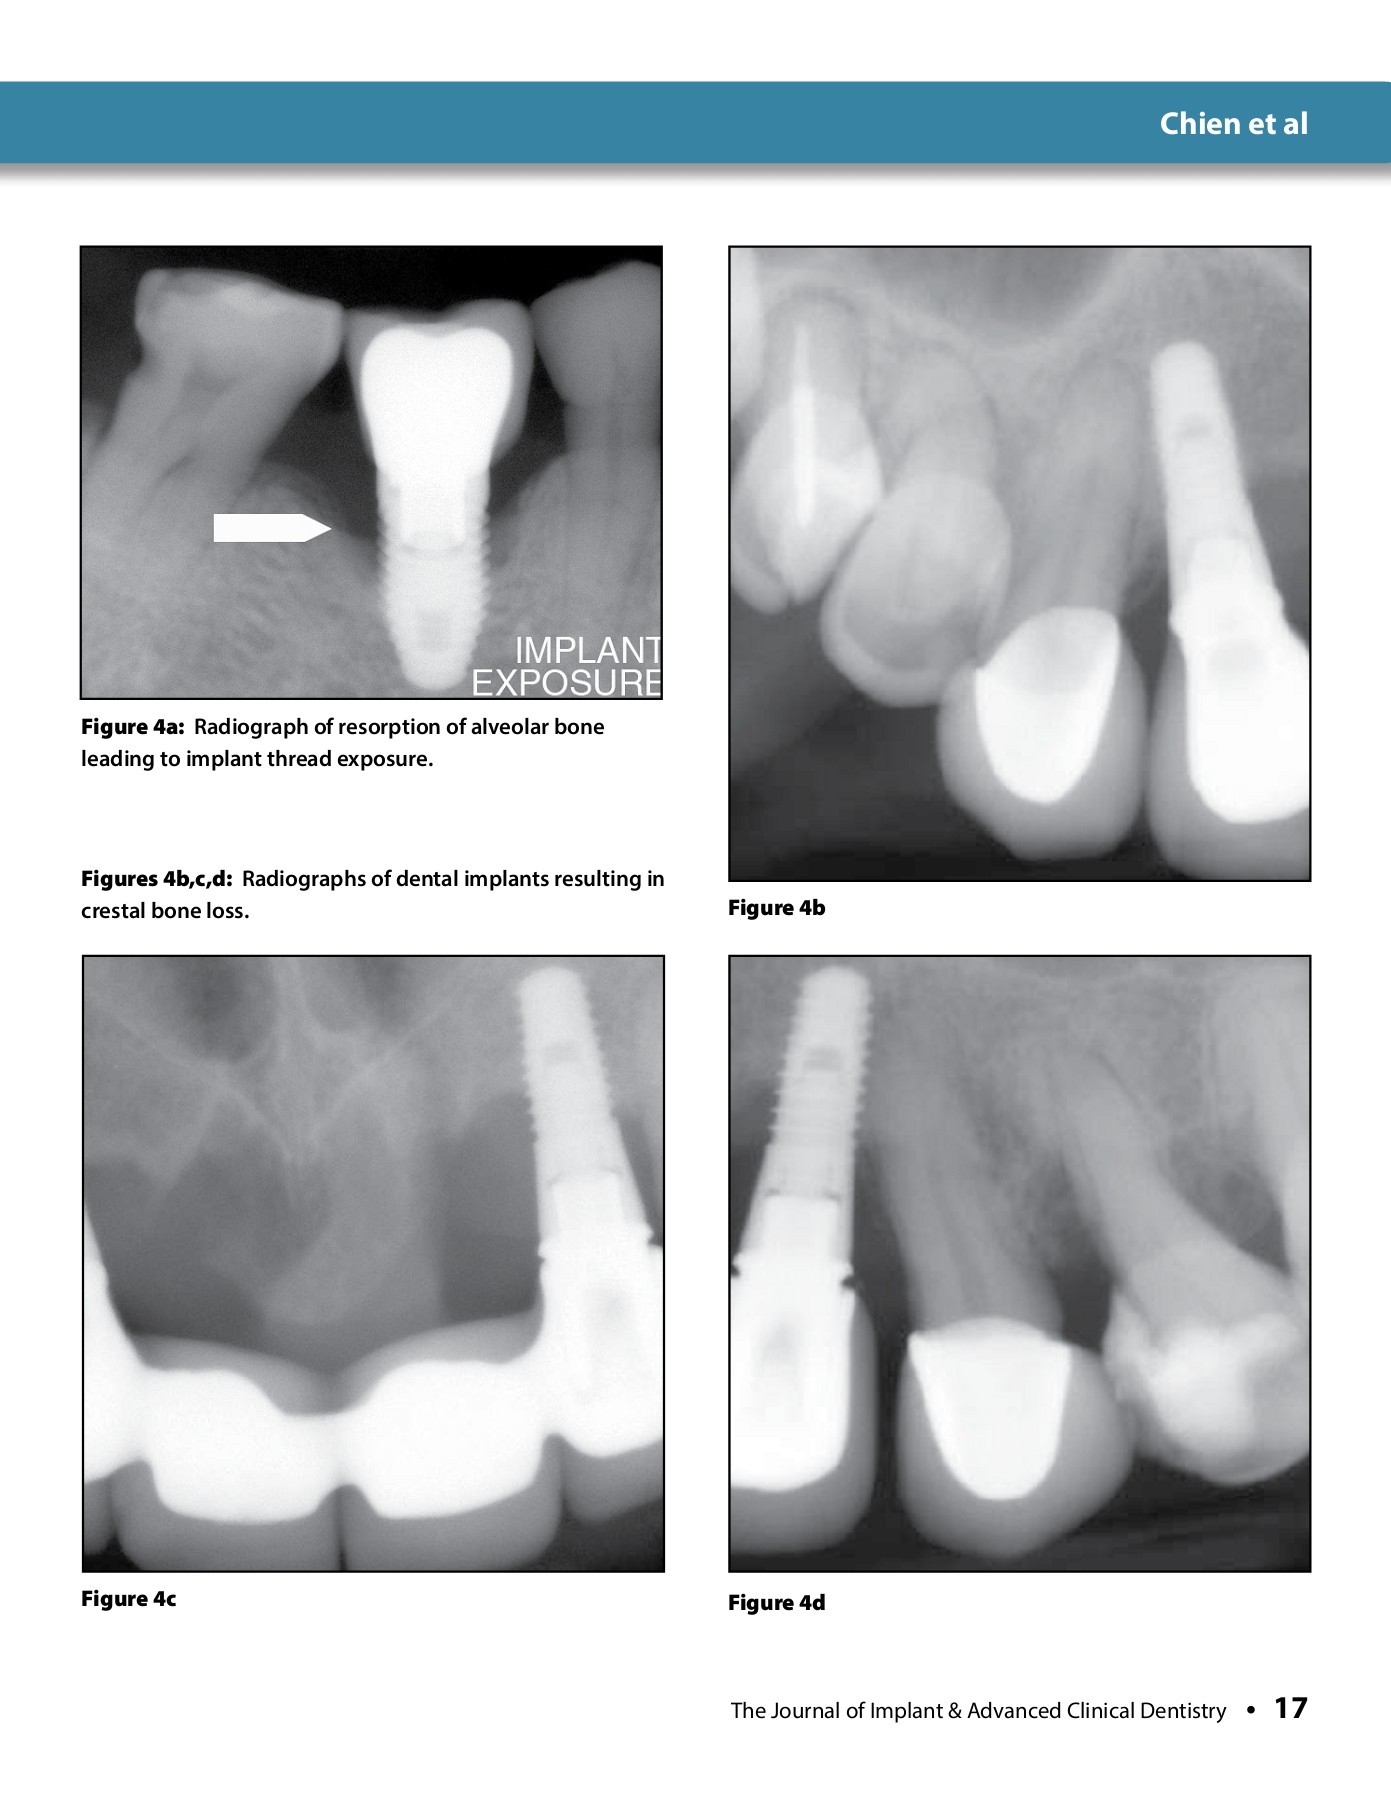

Journal of Implant and Advanced Clinical Dentistry September 2014 Implant Dentistry Journal Dental implants have evolved into a predictable option for replacing missing. clinical implant dentistry and related research aims to advance the scientific and technical developments related to dental implants and related subjects. introduction to dental implants. the journal is dedicated to promoting the exchange and discussion of all research areas relevant to implant. clinical oral implants. Implant Dentistry Journal.